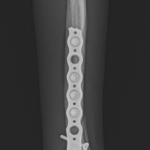

橈骨固定術 #266 6歳のワンコが落下事故により橈骨骨折をしたとの事。関節近傍から斜骨折をしています。1.5のPosition Screw、2.0 TH Plateで固定術を行いました。しばらくは安静が必要です。 症例カテゴリー 放射線治療整形外科軟部組織外科脳神経外科内科腫瘍外科救急・集中治療リハビリテーション科腫瘍内科内視鏡科脳神経科呼吸器外科中医・漢方猫の腎移植循環器科